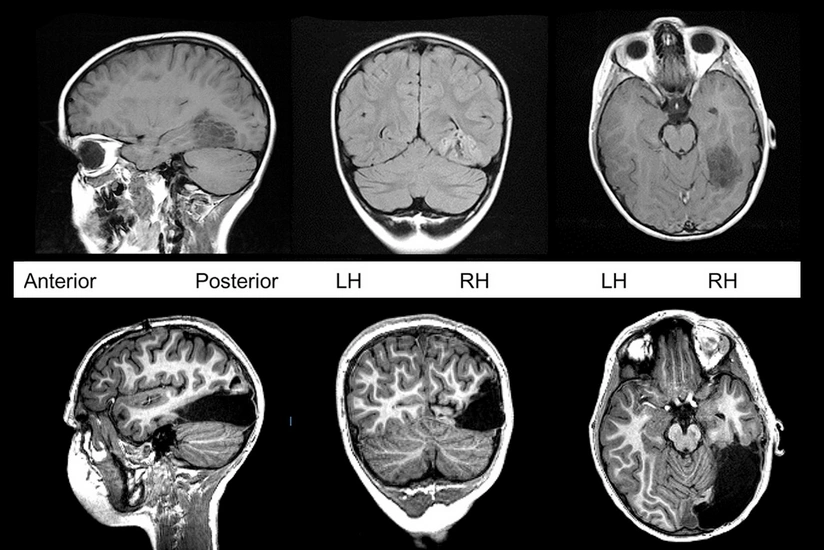

London Universiteti Kollecinin (UCL) tədqiqatçıları COVID-19 üzündən beyin xəstəliklərinin artacağı qənaətinə gəliblər.

“Report” “Brain”ə istinadən xəbər verir ki, məsələyə dair elmi məqalədə koronavirus xəstəliyinin 16-85 yaş arasındakı 43 nəfərdə necə keçdiyi araşdırılıb.

Araşdırma nəticəsində həmin xəstələrin 10 nəfərində beyinin fəaliyyəti müvəqqəti pozulub, 12 nəfərində beyin iltihabı yaranıb. Bununla yanaşı, insult və s. ciddi fəsadlar da özünü göstərib.